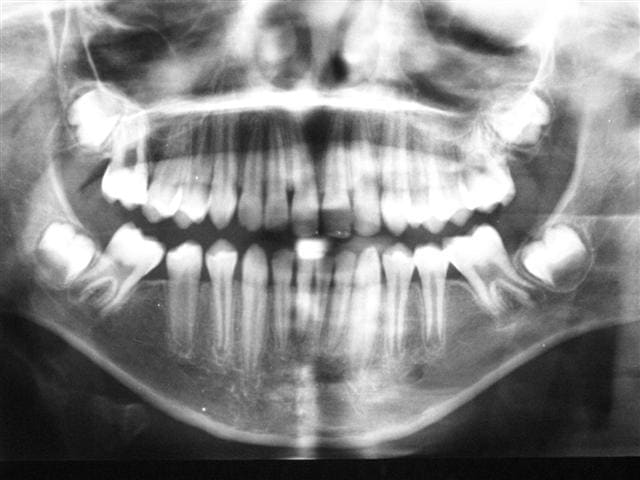

pr apporter de l'eau au moulin de la non conservation des 6 cariées,necessitant TR

extraction des 6 à 9 ans(MIH sur les 6 detruites et 11/21 qui on été refaites en compos)

photos à 12

ce n'est pas parfait à la mandibule mais acceptable car le père n'a pas souhaité faire le ttt odf

à 12 ans il te faudra vraiment convaincre pr l'odf